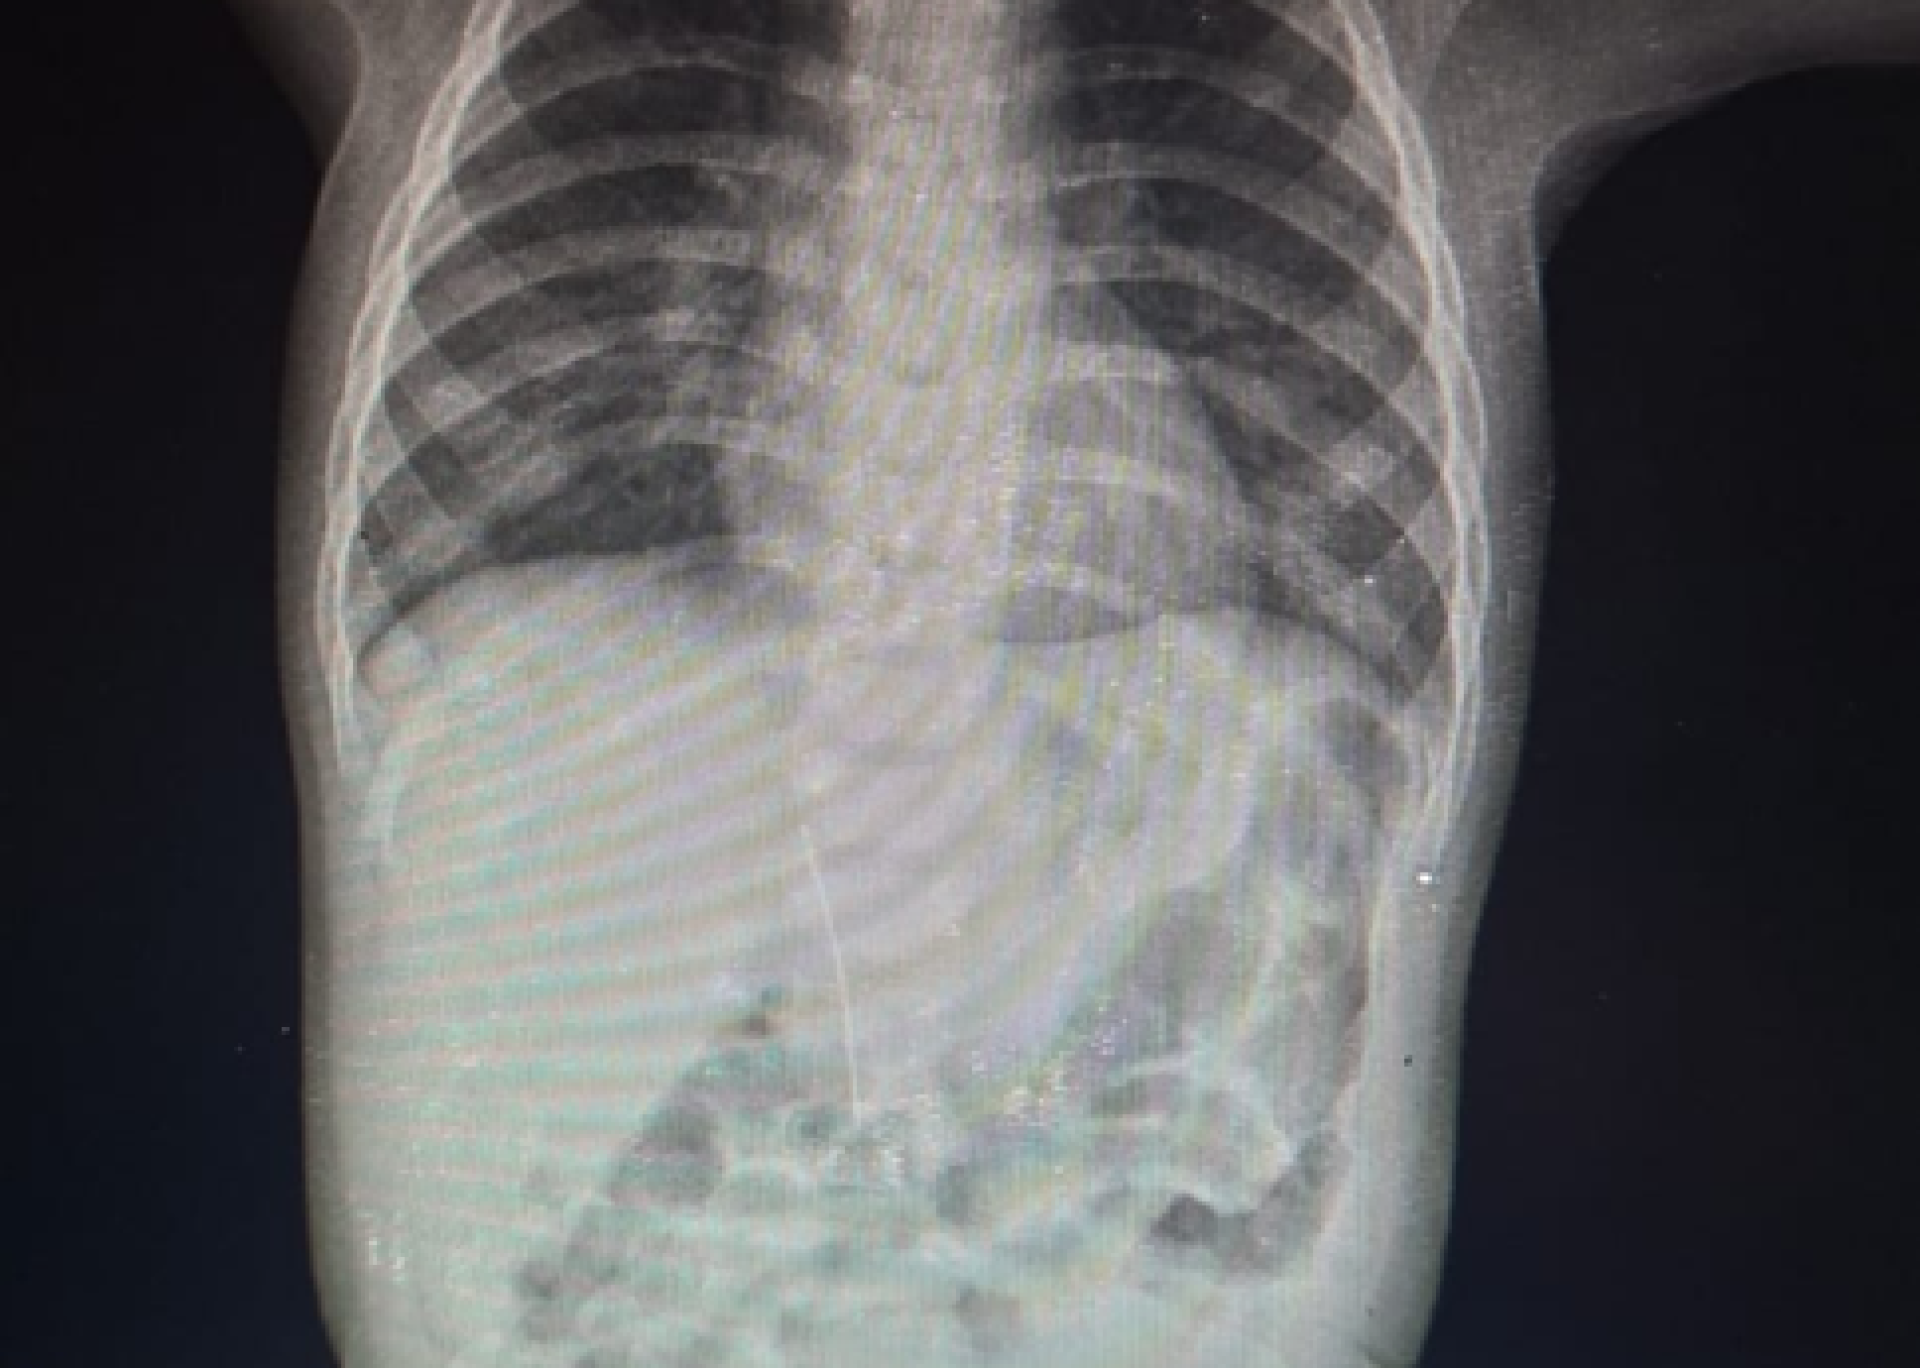

Түркістан қалалық орталық ауруханасының жұқпалы аурулар бөліміне қызамық ауруы болуы мүмкін деген күдікпен 8 айлық сәби жеткізілген. Дәрігерлер рентгендік тексеру жүргізіп, баланың құрсақ қуысынан ине тауып алған, деп хабарлайды Orda.kz.

Бұл туралы бір күн бұрын Түркістан облыстық денсаулық сақтау басқармасының баспасөз қызметі мәлімдеді. Анықталғандай, сәбидің мазасыздануы мен дене қызуының көтерілуі жұқпалы аурудан емес, бөгде заттың әсерінен болған.

Дәрігерлердің айтуынша, ине ағзаға ас қорыту жолы арқылы түспеген. Ол бауыр тұсы арқылы енген. Баланың анасы сәбидің инені өздігінен жұтып қоюы мүмкін еместігін айтқан.

Фото: өңірлік денсаулық сақтау басқармасынан.

Түркістан қалалық орталық ауруханасы мен Түркістан қалалық балалар ауруханасының дәрігерлері бірлесіп шұғыл операция жасап, барлық қажетті емдік шараларды жүргізді. Қазіргі уақытта баланың жағдайы жақсарып келеді, деп нақтылады олар.